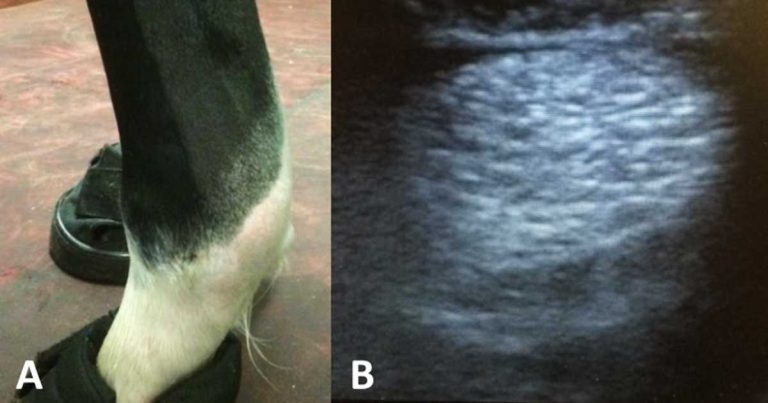

As with any injury, a thorough clinical exam is a crucial part of the assessment. A history of lameness after a period of exercise is a typical complaint. For subtle changes, comparing the affected limb to the contralateral limb provides valuable information (Figure 1).

Comparing the affected limb with the contralateral leg should be done, not only for comparison, but also because palmar lesions can be bilateral in one out of three cases.